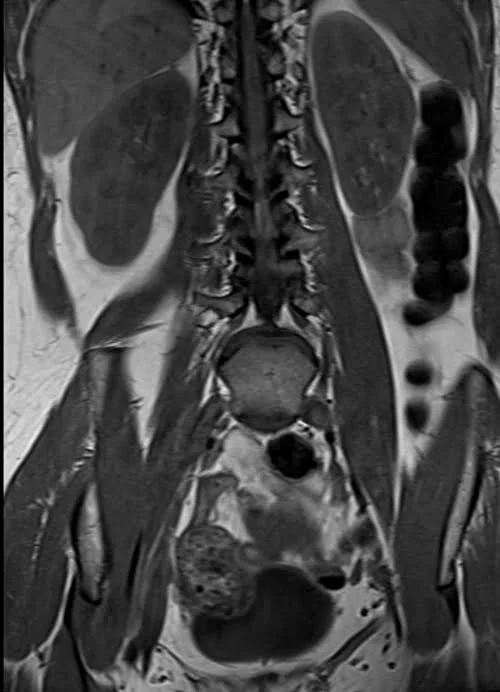

L plexus mri T1 coronal images